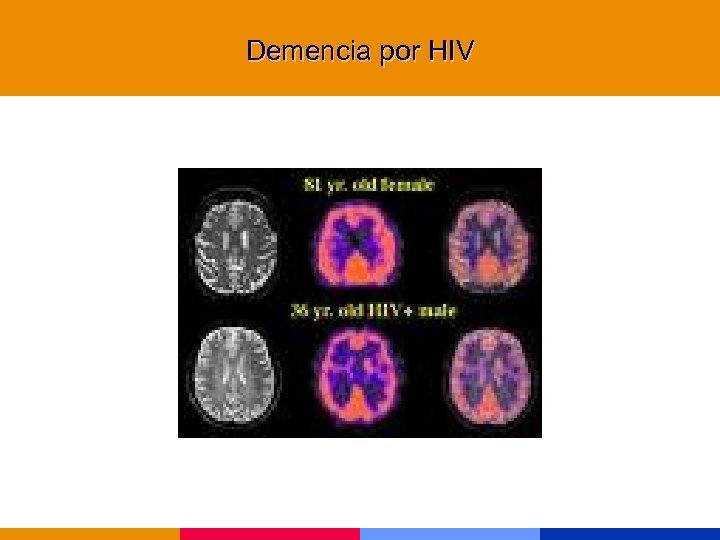

Categoría C (Enfermedades marcadoras) § Encefalitis por HIV, demencia § Neumonía recurrente § Síndrome de desgaste

Categoría C (Enfermedades marcadoras) § Encefalitis por HIV, demencia § Neumonía recurrente § Síndrome de desgaste

Manifestaciones neurológicas en pacientes HIV reactivos § La enfermedad neurológica es la manifestación inicial en el 10 al 20% de los pacientes. § En los pacientes con enfermedad avanzada el 30 a 40% presentará disfunción neurológica durante el curso de la enfermedad. § La incidencia de enfermedad subclínica alcanza al 75 a 90% de los pacientes. J Neurosurgery 1985; 62: 475 -495

Manifestaciones neurológicas en pacientes HIV reactivos § La enfermedad neurológica es la manifestación inicial en el 10 al 20% de los pacientes. § En los pacientes con enfermedad avanzada el 30 a 40% presentará disfunción neurológica durante el curso de la enfermedad. § La incidencia de enfermedad subclínica alcanza al 75 a 90% de los pacientes. J Neurosurgery 1985; 62: 475 -495

Manifestaciones neurológicas en pacientes HIV reactivos § El virus HIV ingresa al SNC precozmente. § La presencia de HIV en SNC no predice el desarrollo de enfermedad neurológica. § El HIV no infecta las neuronas, astrocitos u oligodendroglia. El rol del virus en la demencia es discutido. § La afección probablemente sea producida por citocinas

Manifestaciones neurológicas en pacientes HIV reactivos § El virus HIV ingresa al SNC precozmente. § La presencia de HIV en SNC no predice el desarrollo de enfermedad neurológica. § El HIV no infecta las neuronas, astrocitos u oligodendroglia. El rol del virus en la demencia es discutido. § La afección probablemente sea producida por citocinas

Demencia por HIV

Demencia por HIV